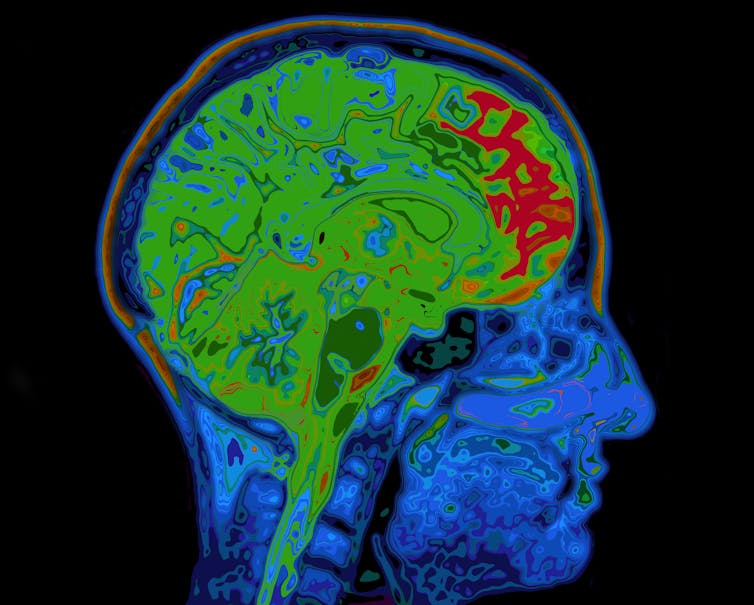

To study glutamate and Gaba, we used a high-strength magnet (called 7-Tesla) to perform magnetic resonance spectroscopy. This technique detects radio frequency electromagnetic signals produced by the atomic nuclei in molecules. This helps scientists to measure what kind of chemicals exist there – and their concentration.

This allowed us to detect and measure glutamate and Gaba levels separately in different brain regions. We specifically looked at two brain regions toward the front of the brain called the anterior cingulate cortex (ACC) and the supplementary motor area (SMA).

We found an imbalance between glutamate and Gaba levels in a group of 31 patients with OCD in the frontal regions of the brain. Specifically, OCD patients had increased levels of glutamate and lower levels of Gaba in the ACC. This means that they had very high levels of neural communication in the area, potentially making it hyperactive. They also had a disrupted balance between these chemicals in the SMA.